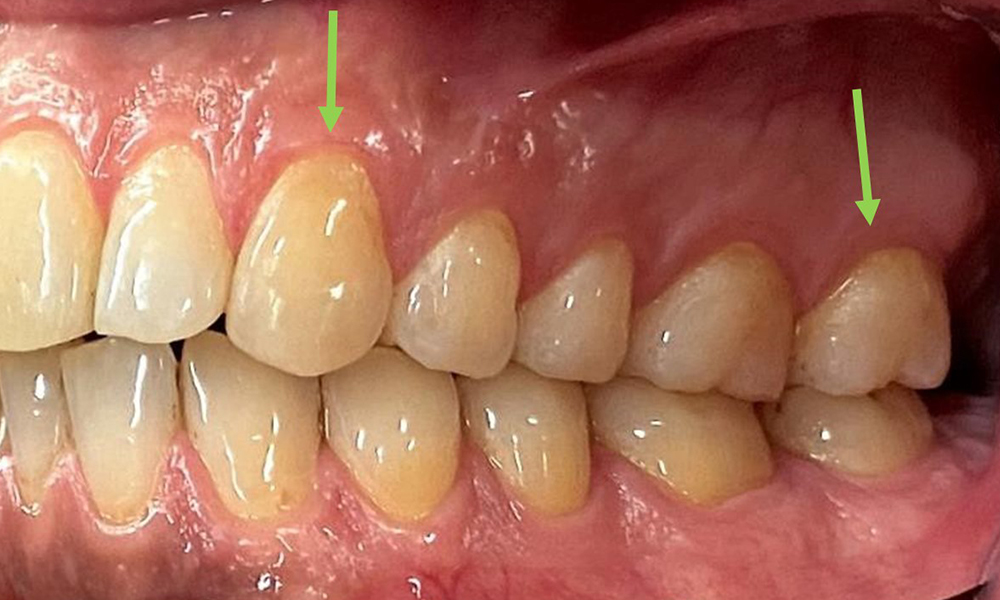

At 1 to 3 mm, the clinical probing depths were within the physiological range. Maxillary recessions of up to 1 mm were observed from 13 to 16 and 23 to 27. The BOP was 15%.